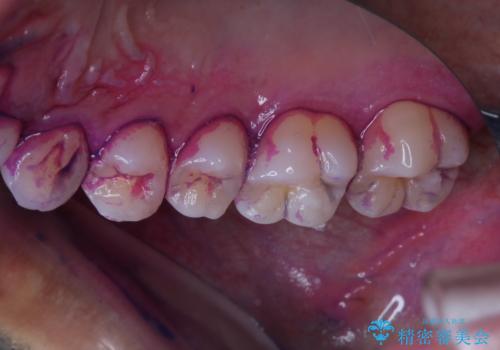

今後、ホームホワイトニング予定との事で、クリーニングPMTC(保険適応外)60分コースを行いました。汚れを取り除き、ご自身の本来の歯の表面になることでツヤがでます。

歯の表面に汚れがついたままホワイトニングを行うと、ホワイトニングの効果が出づらいことがあります。

ホワイトニングご希望の場合は、まずクリーニングを行うことをおすすめします。

汚れがついたままだと、虫歯・歯周病・口臭などの原因にもなります。歯科医院での、定期的なクリーニングを行うことが大切です。